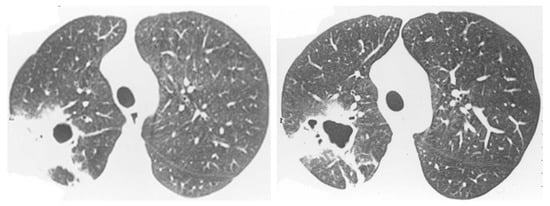

2.2. Non-Resolving Pneumonia

2.3. Chronic Cavitating Disease